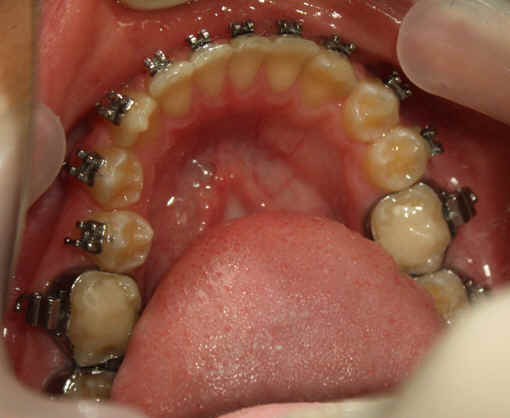

Malpositioned Premolar 13 year-old Caucasian boy

Intra-op 2009/09/10 U wire .018, L .020